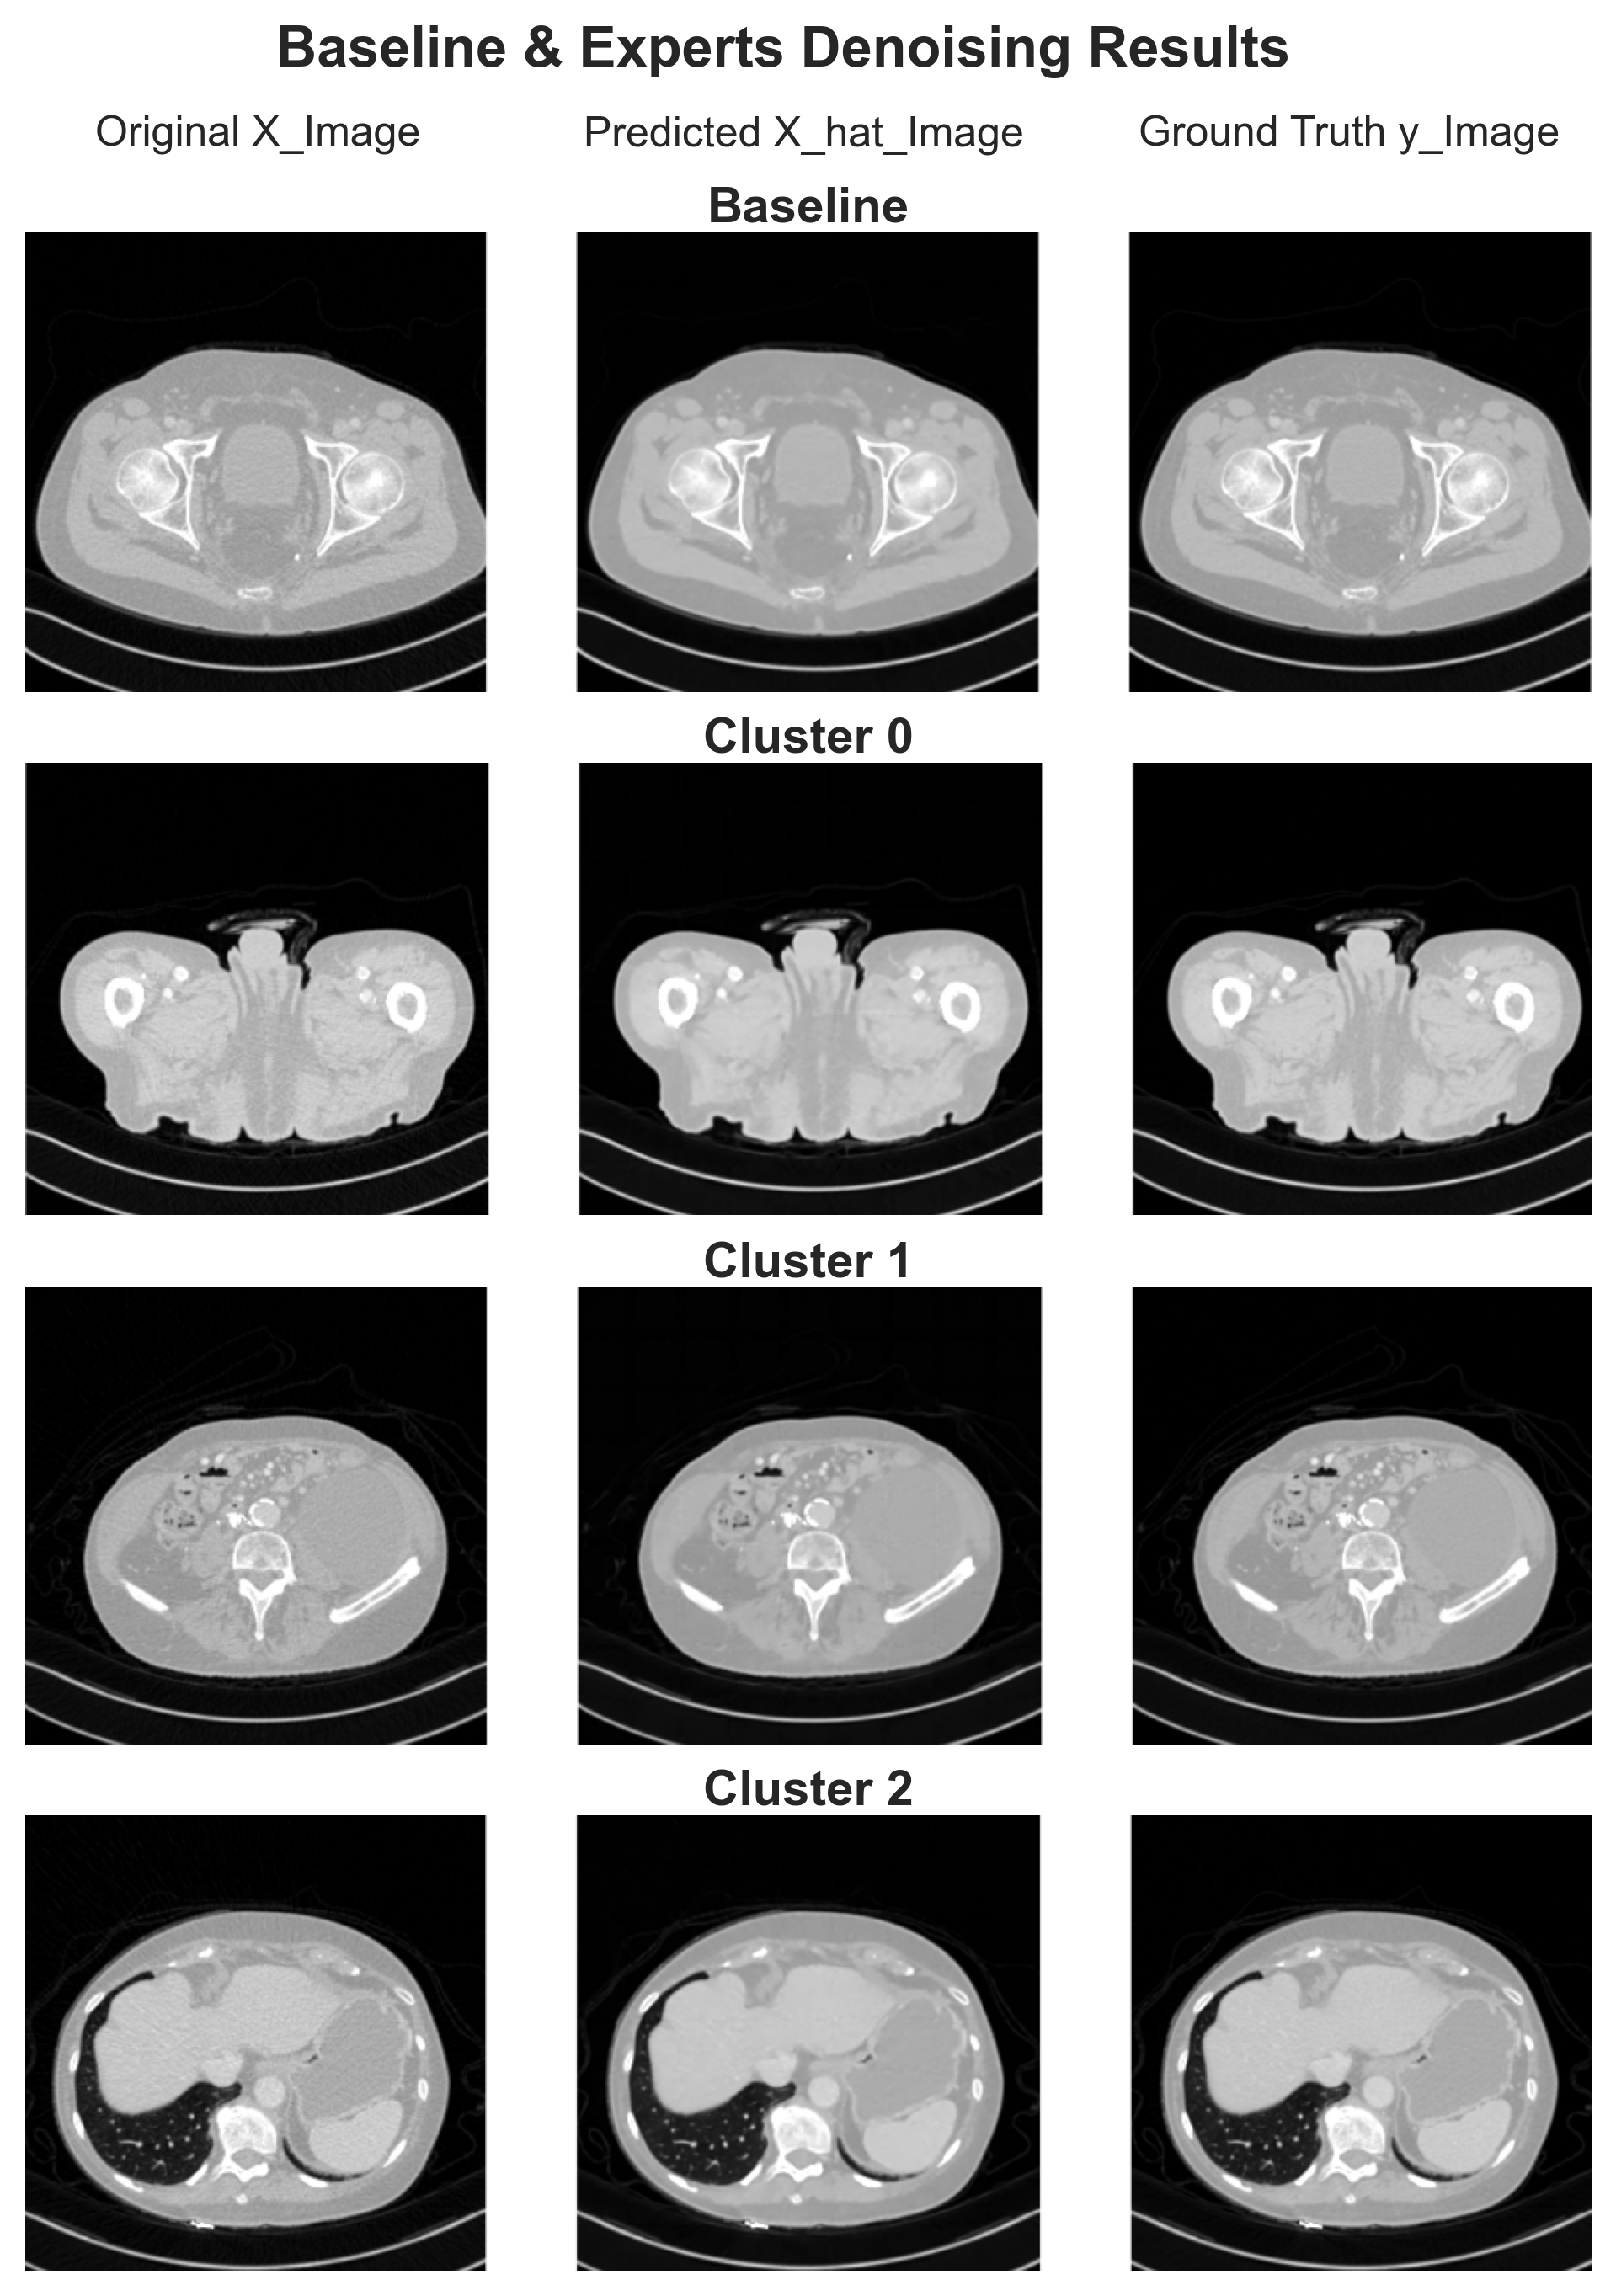

Appendix D Denoising Details

[Uncaptioned image]

Figure 10: Visual comparisons of denoised outputs from the trained models versus the original NDCT images.